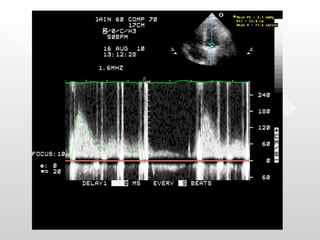

Tracings

What is the differential diagnosis for these tracings? How do we make the diagnosis?